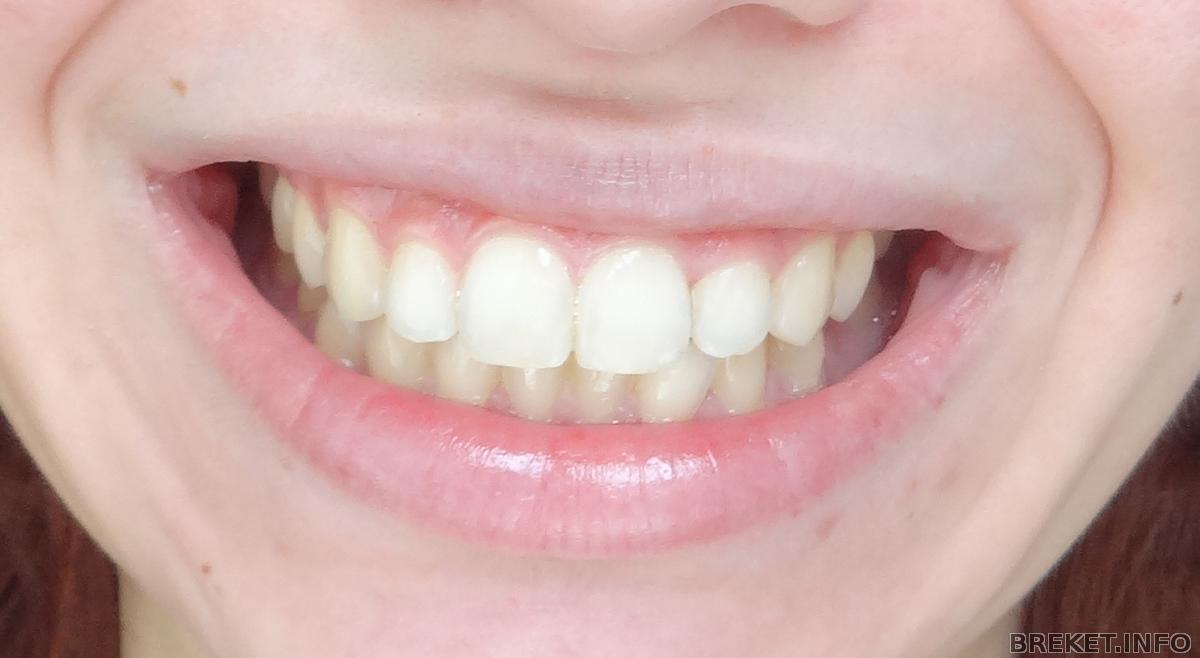

Всем привет! наступил долгожданный день снятия и лечения перед установкой ритейнера. Поставили и заменили на ВЧ 3 пломбы! низ долечим потом. Пришлось пережить много боли. Но зубы теперь неродные какие-то, слишком гладкие, большие... Сохраню привычку чистить зубы после еды на всю жизнь

А вот и результат - даже не верится, к ним так быстро привыкаешь, всего прошел 1 год 1 месяц 25 дней!